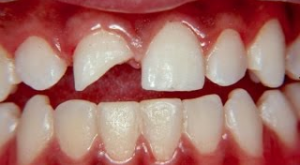

Trauma de concussão Fratura de parte da coroa dentária Frantura da raíz no Raio-x

Outra alternativa é manter em soro fisiológico ou leite e procurar imediatamente seu dentista. Se for apenas uma fratura, fazer o mesmo, pois o fragmento de dente poderá ser colado pelo dentista.